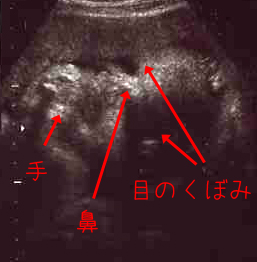

順調に育ってまーす。

<クリックで拡大>

子宮が狭くなってきたのか、

常に「胎児のポーズ」で手が顔の前にあるため

写真写りがどんどん悪くなってきてます。

3Dも毎回試してくれるのですが、形の悪い「餅」みたいなものしか見えない…。

34W1D

★頭の大きさ(横幅)8.83センチ

★体重 2365グラム

やっぱり、2週間で約300グラムのペースで大きくなってます。